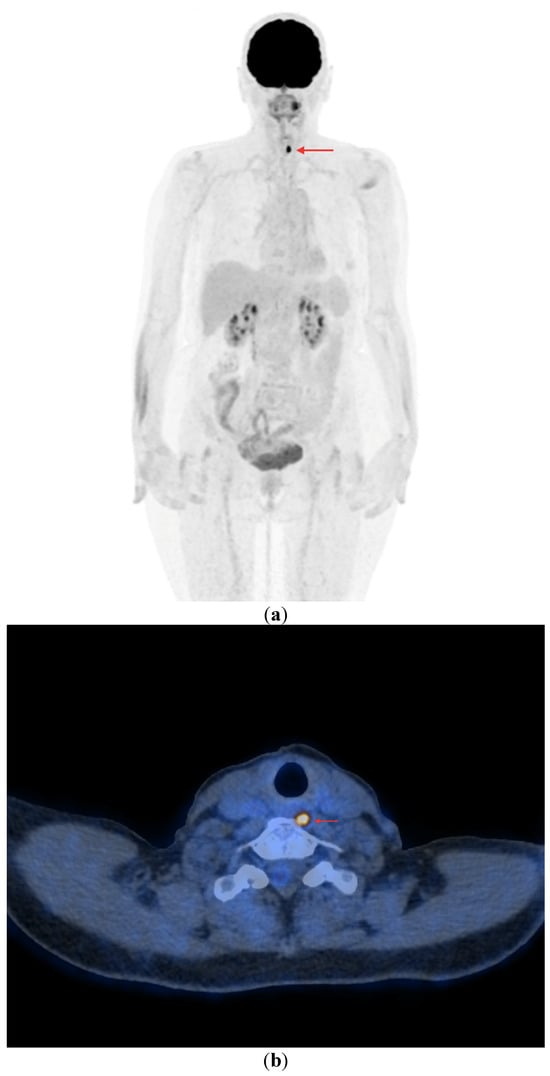

- In the case of non-resectable lesions (due to a lack of the patient’s consent to repeated surgery, lack of technical possibilities of surgery or other reasons), the lesions were verified using FNA only, and after verification, the patients remained in the observation group or were referred to tyrosine kinase inhibitor (TKI) therapy (Figure 4a,b).

Figure 4. PET/CT with [18F]FDG (a) Maximum-intensity projection (MIP). (b) Axial fusion projection. These show an example of accumulation of the [18F]FDG in the left retroesophageal lymph node (red arrow). The lesion was verified as being metastasized DTC using FNA. Due to comorbidities and the patient’s lack of consent, resection of the lesion was abandoned; the patient was left in the observation group, with a stable Tg concentration in follow-up determinations (maximum natTg concentration 3.91 ng/mL, maximum sTg concentration 19.62 ng/mL).